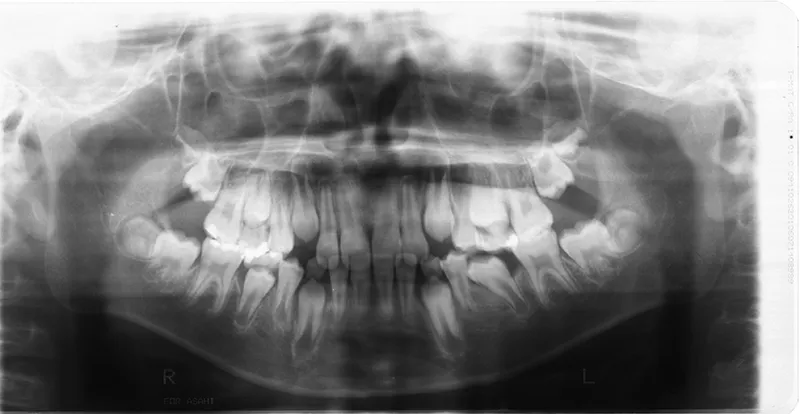

初診時年齢 小学校1年生 (男性) 主訴 すきっ歯・ガタガタ・受け口

診断名 叢生・反対咬合・空隙歯列 装置名

特徴 ゆがんで生えている

状態 永久歯が生える隙間がない(叢生)

受け口(下顎前突/反対咬合)

すきっ歯(空隙歯列)

上の前歯が下の前歯より後ろに入って、受け口になっています。

下の歯は永久歯の生えるスペースがないので、オリジナル矯正装置で受け口を治して、永久歯の生えるスペースを作りました。